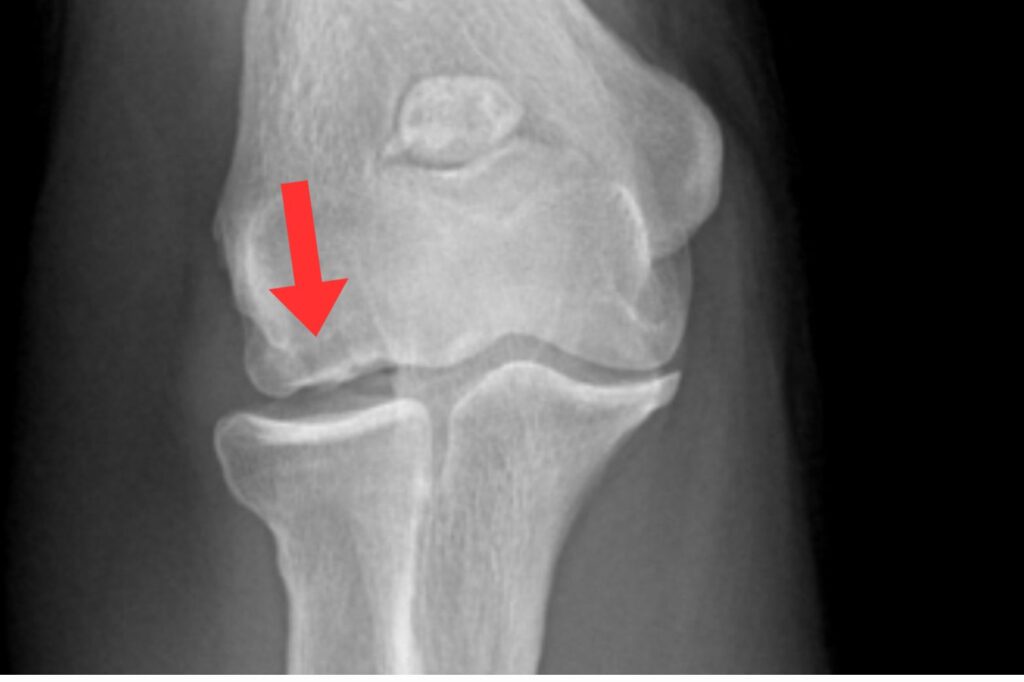

肘の外側のケガ(上腕骨小頭骨軟骨炎)

肘の外側の骨や軟骨が傷み、はがれてしまう状態です。

10代野球選手の[2〜4%]程度にみられるとされています。

初期は痛みが出にくく、

- 肘が伸びきらない

- 引っかかる感じがする

といった症状がサインになることもあります。